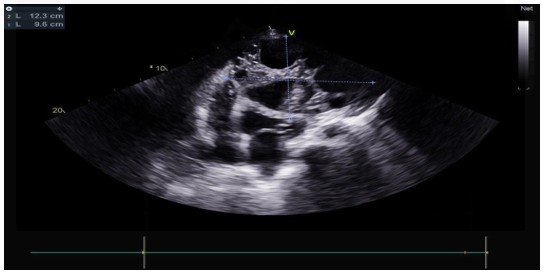

The transthoracic echocardiographic examination revealed (Figures 8 – 18):

- A lobulatedcystic image exerting severe compression on both the right and left cardiac chambers, resulting in hemodynamic disturbance and considerable fluctuation in respiratory flows (Figures 12 – 13,17).

- Left ventricule showed no sign of dilatation. Al though the assessment of contractile function was influeced by compressio from pulmonary hydatid cyst, it appears to maintain functionnality.

- Elevated left ventricular filling pressure were noted.

- The right ventricle exhibited no dilation (Figure 11) despite the presence of longitudinal systolicdys functio n (Figures 14).

- Grade II tricuspid insufficiency was identified, with an estimated systolic pulmonary arterial pressure of 47 mmHg (calculated as 37 + 10 mmHg), indicating the presence of pulmonary hypertension.

- The inferior vena cavademonstrated no dilation (Figure 18) and wasnoted to be non-compliant (Figure 16).

- No pericardial effusion was present.